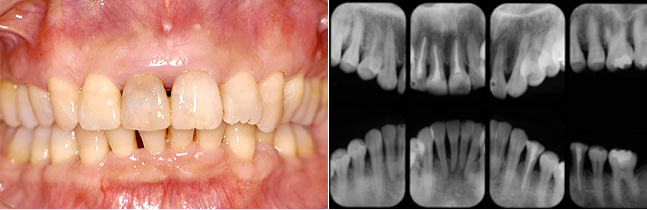

曲がった前歯と歯肉炎に対する治療(28歳・女性)

表からは見えないように歯の裏からの矯正治療

治療前

治療前は前歯のゆがみ、歯肉の炎症、奥歯の欠損・虫歯などいくつもの悩みを抱えておいででした。

歯周治療と矯正治療、臼歯部はセラミッククラウンによってきれいな歯列に戻すことができました